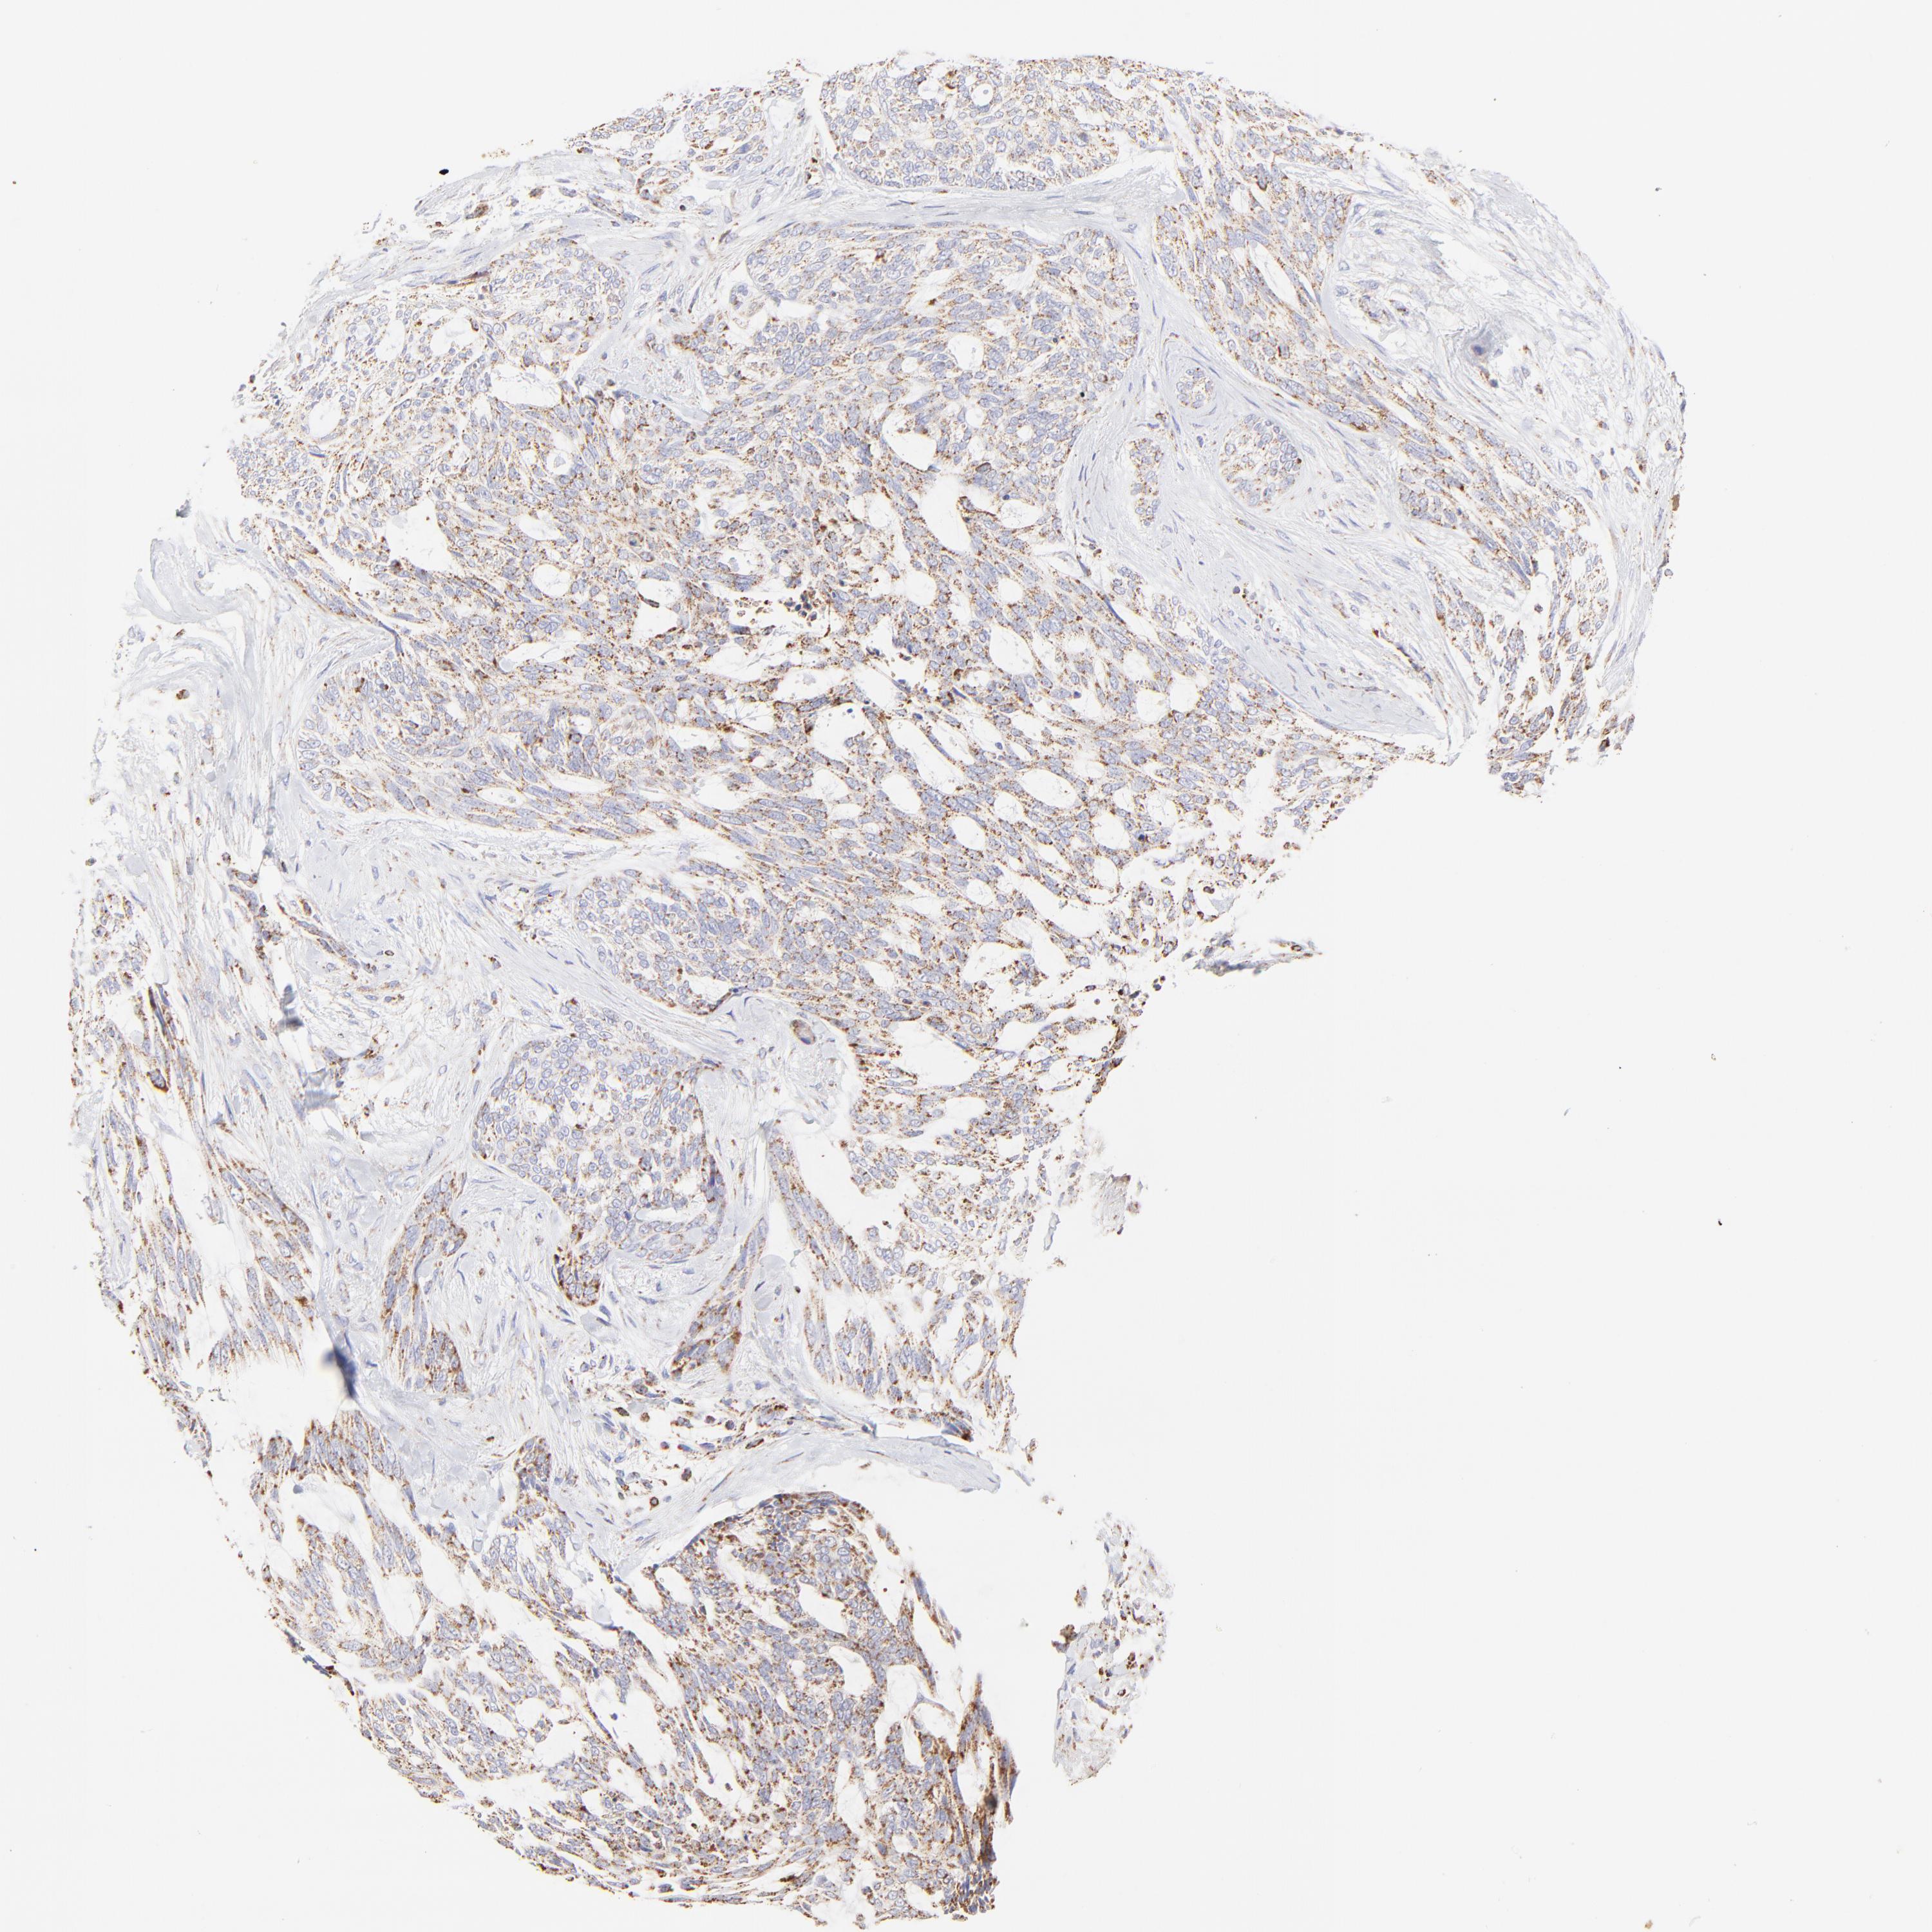

SKIN CANCER - Protein expressioni

A mouse-over function shows sample information and annotation data. Click on an image to view it in a full screen mode. Samples can be filtered based on level of antibody staining by selecting one or several of the following categories: high, medium, low and not detected. The assay and annotation is described here.

Antibody stainingi

Antibody staining in the annotated cell types in the current human tissue is reported as not detected, low, medium, or high, based on conventional immunohistochemistry profiling in selected tissues. This score is based on the combination of the staining intensity and fraction of stained cells.

Each image is clickable and will lead to virtual microscopy that enables deeper exploration of all samples and also displays staining intensity scores, fraction scores and subcellular localization as well as patient and tissue information for each sample.

Antibody HPA002907

Squamous cell carcinoma, NOS